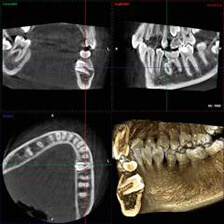

歯科用CT

CT(Computed Tomography)とは、コンピューター断層撮影を意味します。CTは、X線とコンピューターによって、歯や骨の位置や形態などを立体的(3D)に撮影することができます。

血管や神経の位置を立体的に把握し、骨量、骨密度を正確に確認できるため、インプラント治療の際にはCTによる診査・診断が必須となっています。

また、CTは、インプラント治療だけでなく、さまざまな歯科治療の精度向上に役立ちます。歯、血管、神経の位置だけでなく、歯槽骨の状態や根管の形態等もより正確に把握することができるため、埋伏歯抜歯、矯正治療、根管治療、歯周病治療などで、より正確な診査・診断、治療の予知性を高度化を実現することができます。